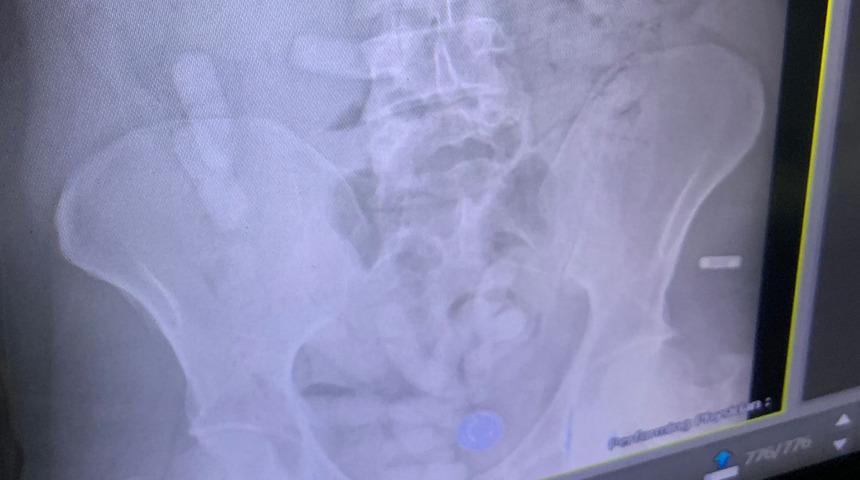

Aramada yolculardan İran uyruklu A.E.'nin (34) üzerinde 140 paket reçine esrar ile 6 uyuşturucu hap bulundu. Gözaltına alınarak röntgen filmi çekilen şüphelinin midesinde 15 paket daha reçine esrar bulunduğu belirlenerek doğal yollarla çıkarılması sağlandı.

Toplamda şüphelide 1 kilo 395 gram reçine esrar ile 6 uyuşturucu hap ele geçirildi. Gözaltına alınan şüpheli, jandarmadaki işlemlerinin ardından çıkarıldığı mahkemece tutuklandı.